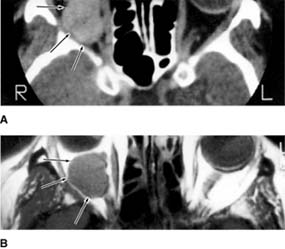

CAVERNOUS HEMANGIOMA (Figure 13-7)

Cavernous hemangiomas are benign, grow slowly, and usually become symptomatic in middle life. Most occur in women. They most often lie within the muscle cone, producing axial proptosis, hyperopia, and, in many cases, choroidal folds. Unlike capillary hemangiomas, they do not tend to regress spontaneously. Surgical excision is usually successful and is indicated if the patient is symptomatic.

Figure 13-7

Figure 13-7: Cavernous hemangioma (arrows) of the right orbit as demonstrated by both CT scan (A) and MRI (B). The left side demonstrates the appearance of a normal orbit and globe. (Courtesy of D Char.)

new window Figure 13-7: Cavernous hemangioma (arrows) of the right orbit as demonstrated by both CT scan (A) and MRI (B). The left side demonstrates the appearance of a normal orbit and globe. (Courtesy of D Char.)